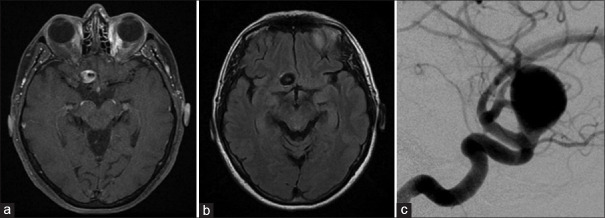

血流分流支架越来越多地用于颅内动脉瘤的治疗,特别是当存在不利于线圈栓塞的因素时,如颈部宽和动脉瘤尺寸大。然而,它的使用并不能保证成功,特别是在巨大病变中,未能获得动脉瘤闭塞会导致动脉瘤壁长期不稳定,导致动脉瘤生长和晚期破裂。我们提出的情况下,65岁的妇女谁遭受晚期动脉瘤扩张和破裂,2年零4个月后,分流治疗巨大的眼段动脉瘤。虽然尚未完全了解,但这种现象的病理生理学有一个必要因素:不完全的动脉瘤闭塞。当出现这种情况时,主要有两个因素:支架置入后囊内血流的增加以及部分血栓形成和支架本身的存在引起的局部炎症。为了防止这种并发症,必须确保动脉瘤完全闭塞,并鼓励使用联合技术。

Flow-diverting stents have been increasingly utilized for the treatment of intracranial aneurysms, especially when there are factors that go against coil embolization, such as wide neck and large aneurysm size. However, its use does not guarantee success, especially in giant lesions, and failure to obtain aneurysmal obliteration can result in long-term instability of the aneurysmal wall, leading to aneurysmal growth and late rupture. We present the case of a 65-year-old woman who suffered from a late aneurysmal dilation and rupture, 2 years and 4 months after flow-diverting treatment of a giant ophthalmic segment aneurysm. Although not fully understood, the pathophysiology of this phenomenon has one necessary factor: incomplete aneurysmal obliteration. When this scenario is present, two main factors take place: the augmentation of intrasaccular blood flow after stent delivery and the local inflammation caused by partial thrombus formation and the presence of the stent itself. To prevent this complication, complete aneurysmal obliteration must be assured, and the use of combined techniques is encouraged.